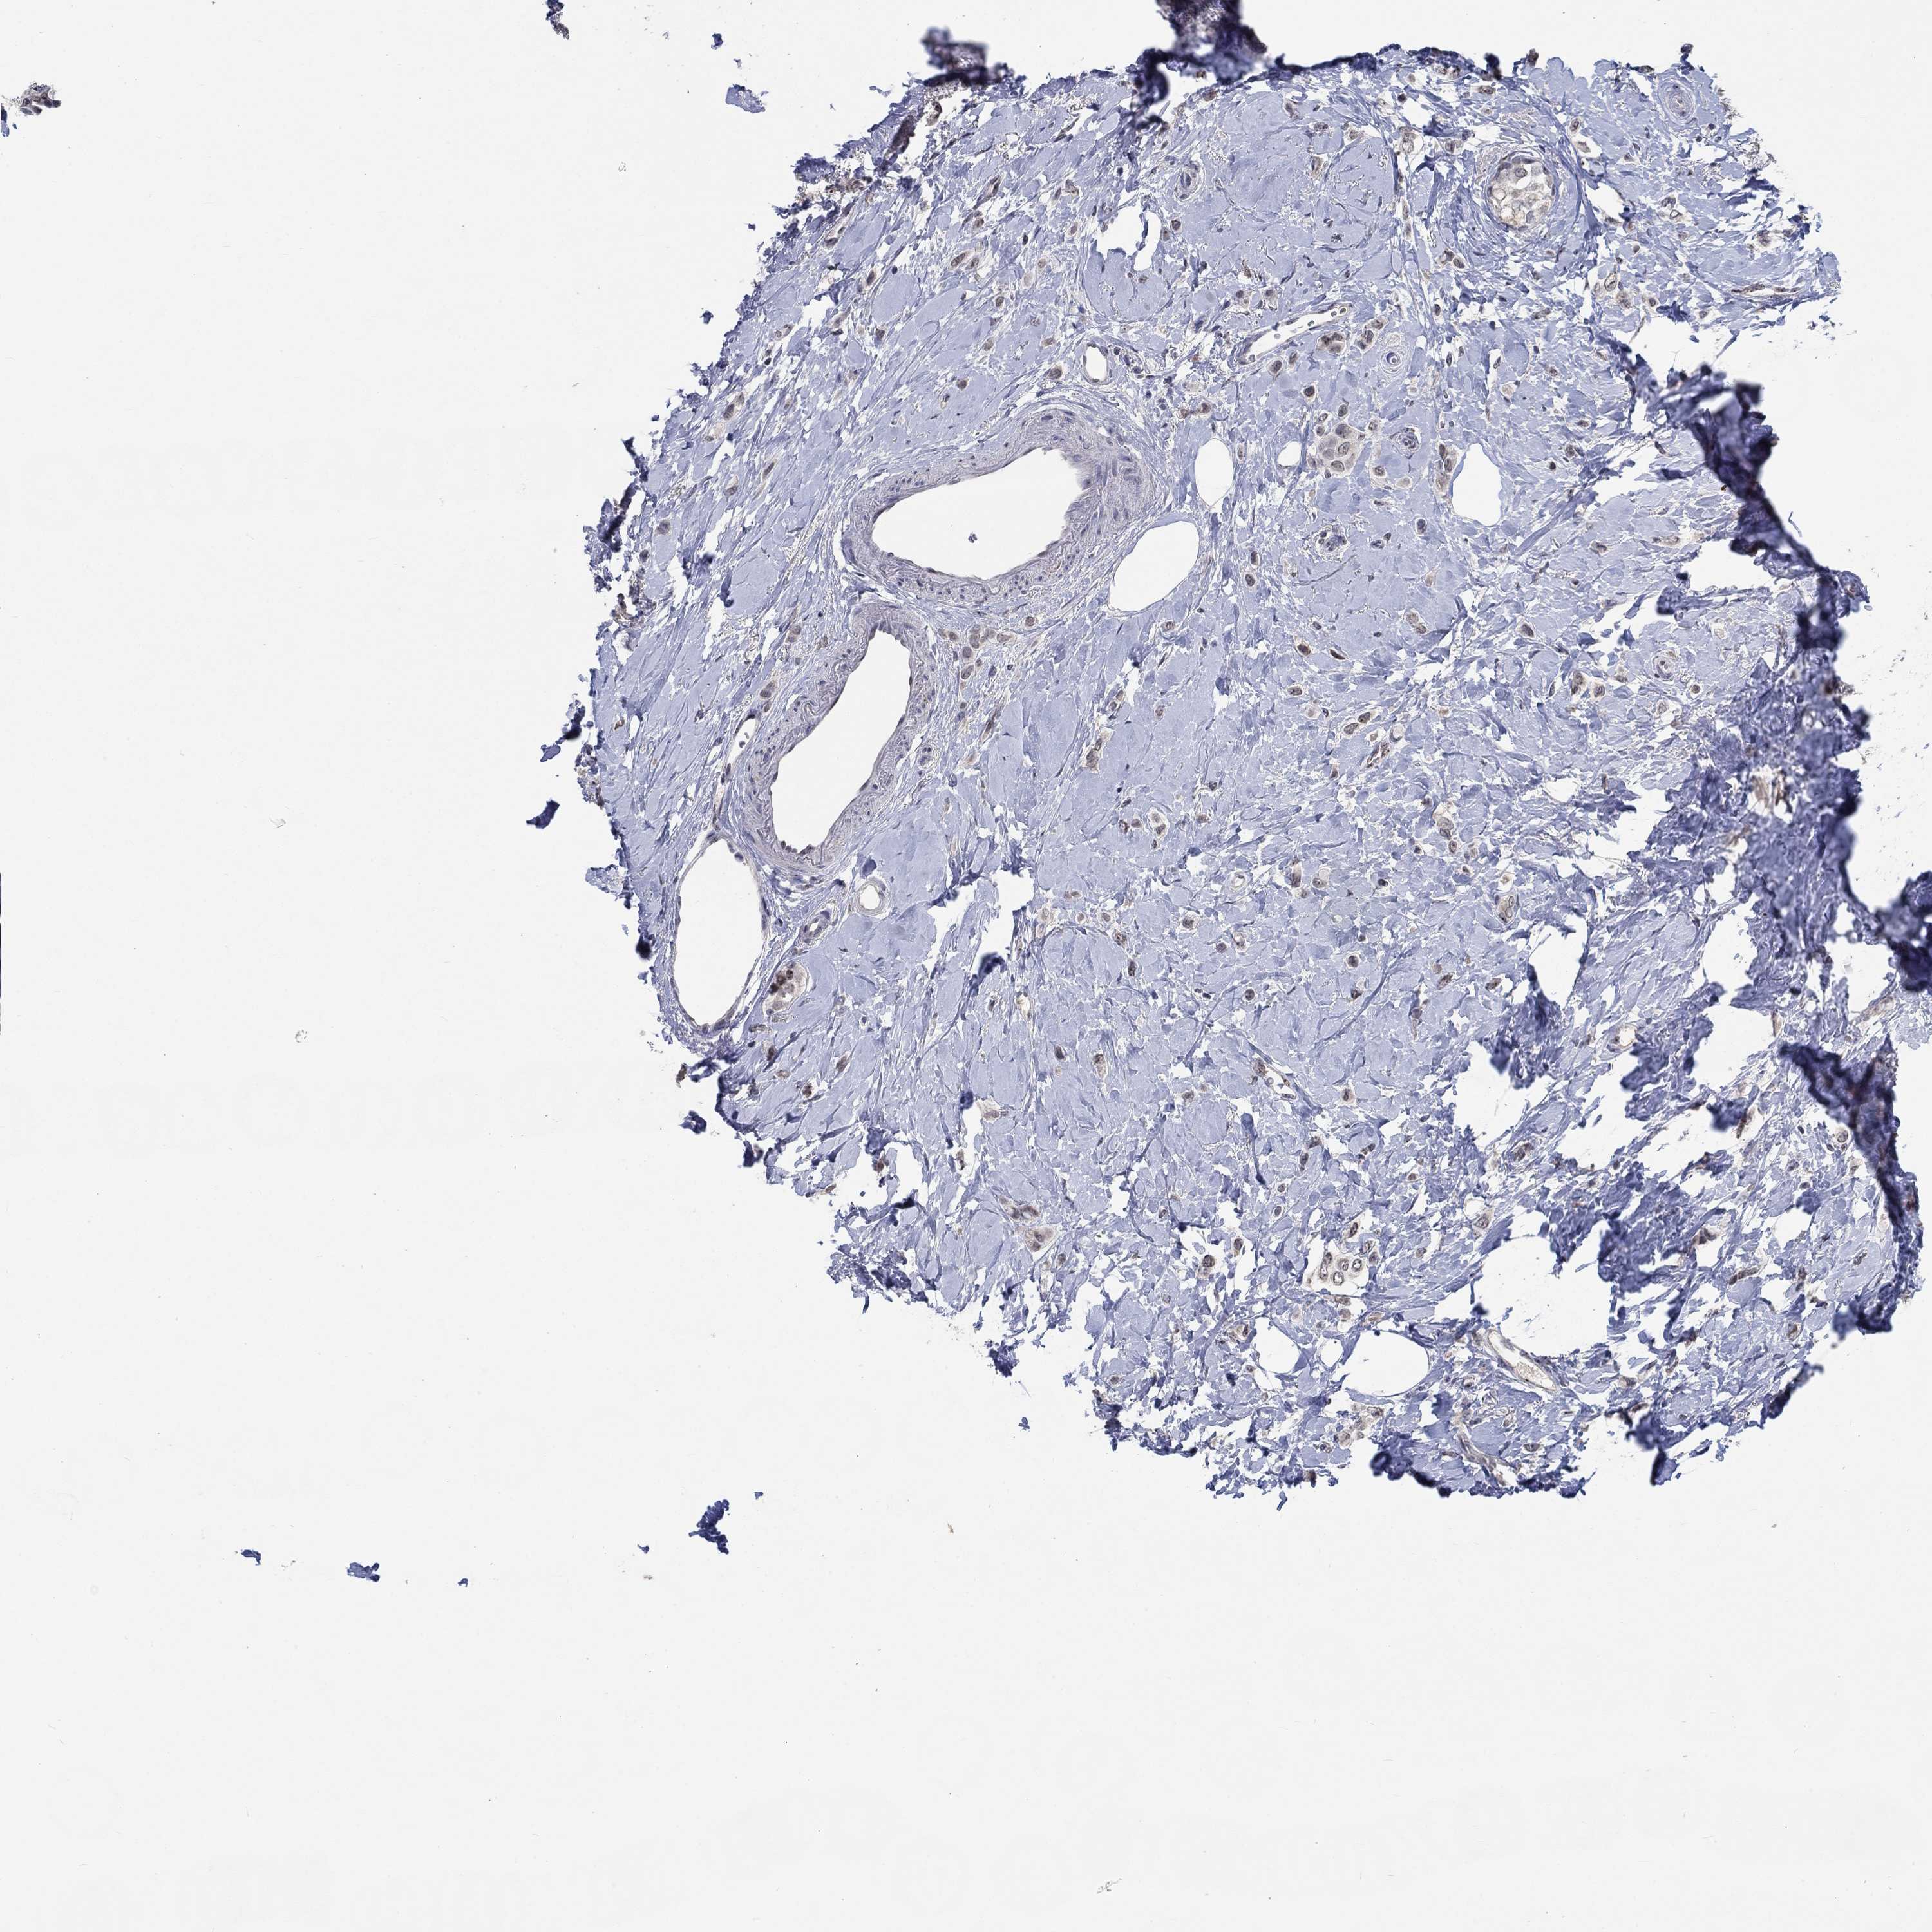

CANCER BREAST CANCER Show tissue menu

Breast cancer

Human cancer